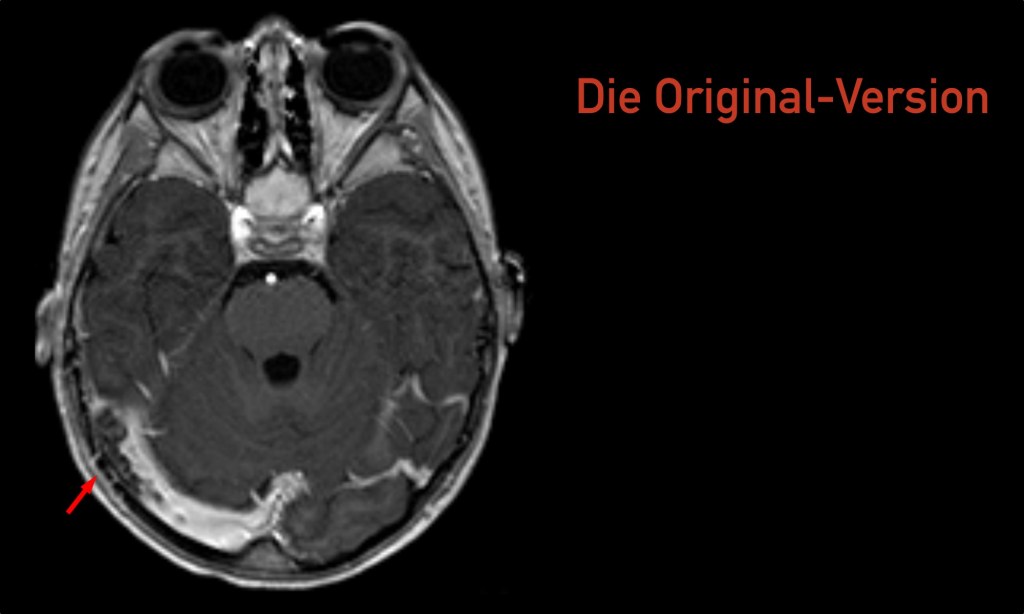

Vorwort Ja, wir sind keine Radiologen. Ja, in der heutigen Zeit, in der es immer mehr um medikolegale Konsequenzen unseres Tuns geht, sollten wir uns nicht überschätzen und selbst radiologische Befunde erheben ohne die formale Qualifikation dafür zu haben. Ja, auch fachärztliche radiologische Befunde sind oft falsch (oder mindestens diskutabel). Ja, ich erwarte von allen…